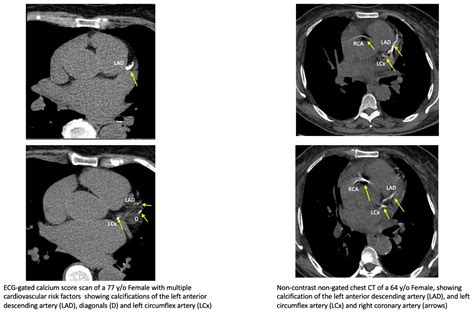

The Cac Score Test is a rapid, non-invasive imaging procedure used to detect the presence and amount of calcified plaque in the coronary arteries. Calcium deposits in the heart are a strong indicator of atherosclerosis—the hardening and narrowing of the arteries due to plaque buildup. When plaque builds up, it restricts blood flow to the heart muscle, significantly increasing the risk of a heart attack.

Unlike invasive procedures, this test does not require needles, dyes, or hospitalization. It is essentially a specialized CT scan that captures images of your heart in just a few minutes. The resulting "calcium score" provides a quantitative measure of your cardiovascular risk, moving beyond simple risk factors like age or family history to provide a tangible snapshot of your actual arterial health.

Once the scan is complete, a radiologist analyzes the images to calculate your score. The score represents the total volume of calcium detected across all coronary arteries. The higher the number, the greater the extent of plaque buildup and the higher the associated risk of cardiovascular events.